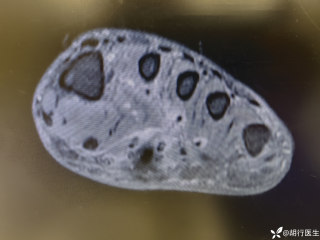

烧伤整形邹普功烧伤科医师

活动背景和目的:我从去年九月份陆续在丁香园写了几十帖有关腋臭微创手术的帖子,受到很多同行老师的关注及跟帖,其中有很多同行老师也在尝试用我的这种方法治疗狐臭,并且收到很好的效果。随着站内外科同行对狐臭微创手术的关注度日渐增高,近期受丁香园邀请,特举办一次关于狐臭微创手术的跟学练活动。这也是本人根据临床工作中的一些手术案例总结的经验,分享给大家一起交流学习。让我们一起做好除臭这件事!各位站友可点击下面狐臭专场链接交流学习(包含本人视频操作教学详解、常见问题讨论和各位站友同行的手术佳作):https://3g.dxy.cn/newh5/view/nodeActivityTopic/270第一期我给大